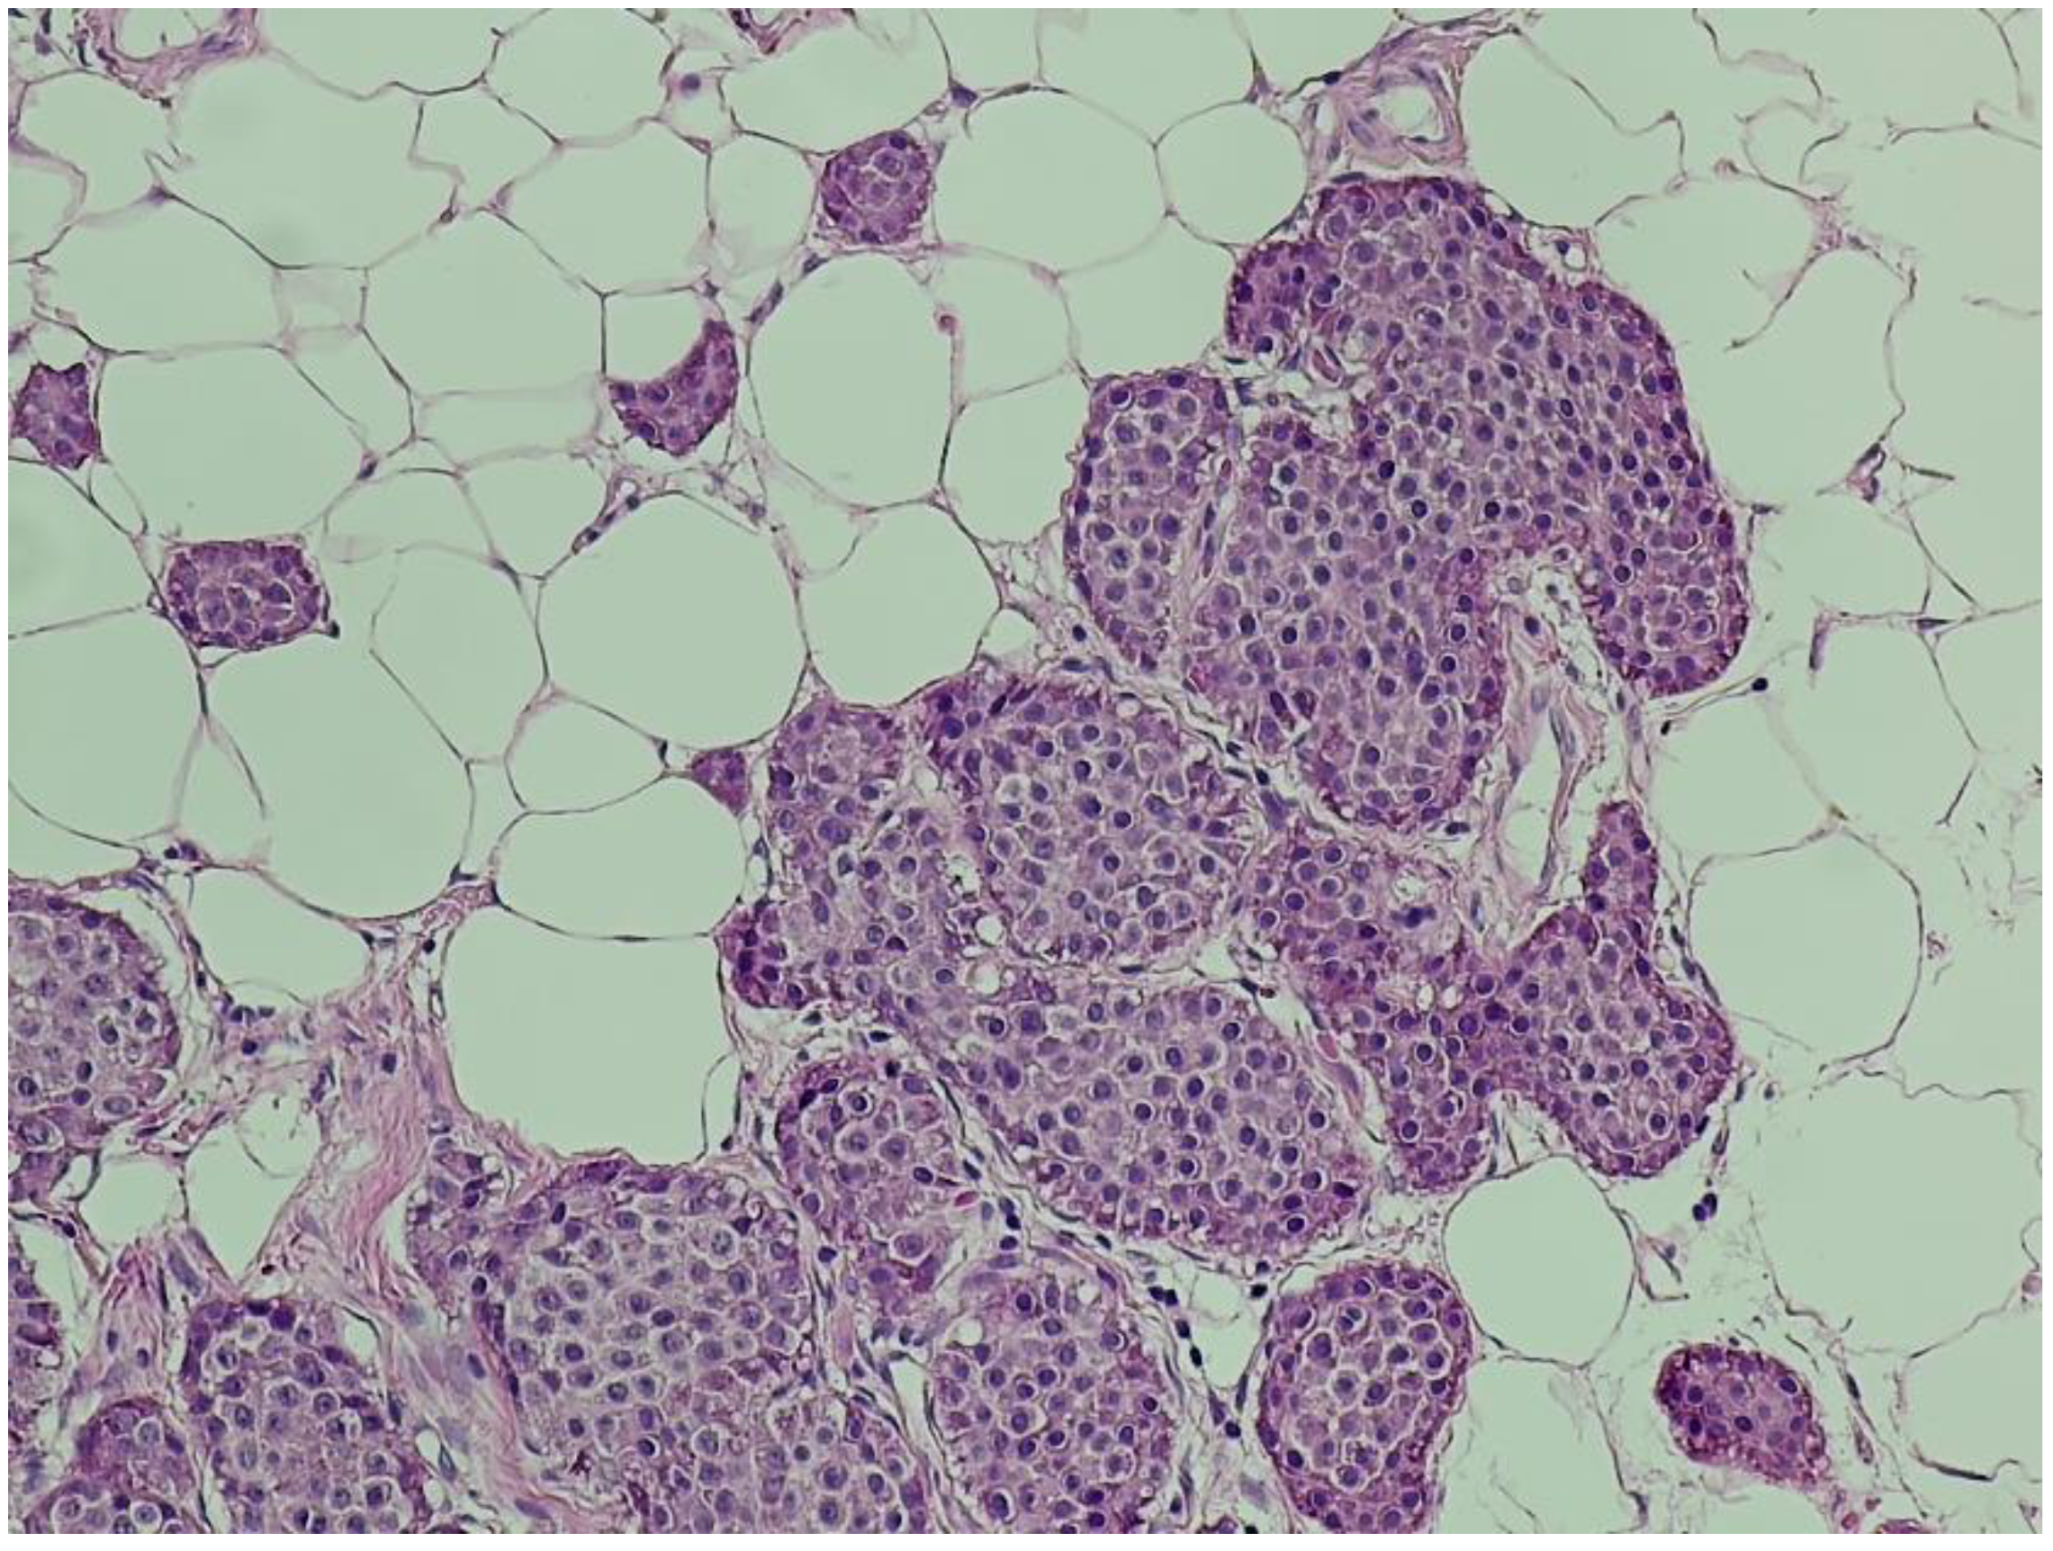

• A 5 cm mesenteric mass in the pelvic region (Figure 1A).

• Multiple hypodense hepatic nodules compatible with liver metastases (Figure 1B).

Figure 1. (A,B): Contrast-enhanced abdominal CT. (A) A pelvic mesenteric tumor mass (yellow arrow) is seen causing significant dilatation of adjacent small bowel loops, suggestive of partial obstruction. (B) Multiple hypodense hepatic lesions (yellow arrow) are visualized, consistent with secondary metastatic deposits from a neuroendocrine tumor.